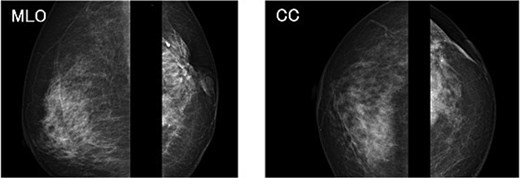

The mammography examination did not reveal any obvious abnormal findings in the right breast (Fig. 1). The breast ultrasound examination also did not reveal any obvious abnormal findings in the breast. The chest computed tomography examination revealed a lymph node that had enlarged to 46 × 34 mm in the right axilla (Fig. 2). There were no enlarged lymph nodes in the mediastinum, hilar region or supraclavicular fossa, and there were no signs of distant metastasis. Magnetic resonance imaging (MRI) of the breast showed no lesions in the right breast, and a lymph node 46 × 34 mm in size was found enlarged in the right axilla (Fig. 3).

Chest radiograph (frontal view). No obvious abnormal findings were observed in the right breast.